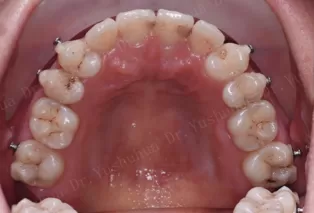

Photos intra-orales